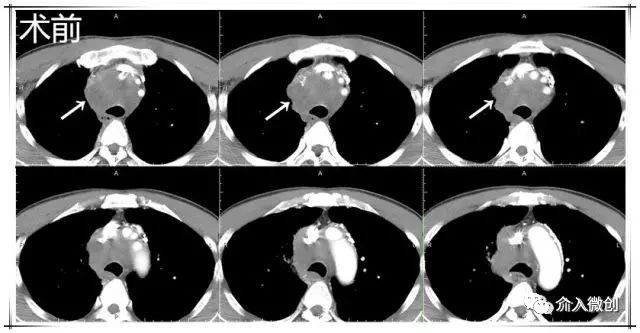

- 增强CT示右前上纵隔肿物,侵犯压迫上腔静脉;PET-CT显示右前上纵隔高代谢病灶。

术前CT显示纵膈肿物,包绕、压迫纵膈血管

术后1个月复查CT显示纵隔肿瘤较前明显缩小,临床症状明显缓解